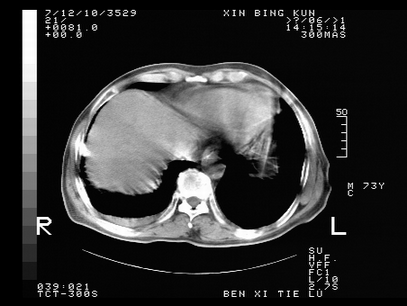

标题: CT10820:男,73岁,病史肺TB,现病史肺炎,直肠CA术后 [打印本页]

标题: CT10820:男,73岁,病史肺TB,现病史肺炎,直肠CA术后

双肺间质改变,依据病史双肺多发结节灶考虑转移,少量胸水.

1.两肺结核.2.两肺多发转移瘤.3右侧少量胸腔积液4.主动脉钙化.

双肺多发结节及条片状致密影,右侧少量胸腔积液。临床:直肠ca术后,肺tb病史。综合考虑:1 双肺转移!2 继发性肺结核合并感染!

此人病史较复杂,原有肺结核,直肠癌术后。肺部病灶形态亦呈多形性。因此,不可仅以一种病来解释肺部的病变。双肺多发的类圆形结节灶,结合病史还是首先考虑转移瘤,而双肺其余病灶还需结合化验室检查,结核或肺部感染在无其它检查资料的情况下不好排除。还是那句话----放射科医生不是开照像馆的,我们也是医生,看片一定要多结合临床及其它检查资料。要当一名合格的放射科医生,并不比当一名临床医生容易,我们可别把自已不当医生看。

两肺多发结节影,并见滋养动脉与其相连,考虑 两肺转移. 右侧胸腔积液考虑胸膜转移.

左肺上叶下叶背段,右肺中下叶见多发斑片状、条索状高密度影,兵变周围小结节影形成“树芽”样改变。 左肺上叶舌段近前胸壁处及右肺中叶内侧段见结节影。右侧胸膜腔内见液体密度区。纵隔内未见明确增大淋巴结。考虑左肺上叶舌段近前胸壁处及右肺中叶转移瘤可能性大。两肺继发型肺结核。右侧胸腔积液。

还有心包少量积液。